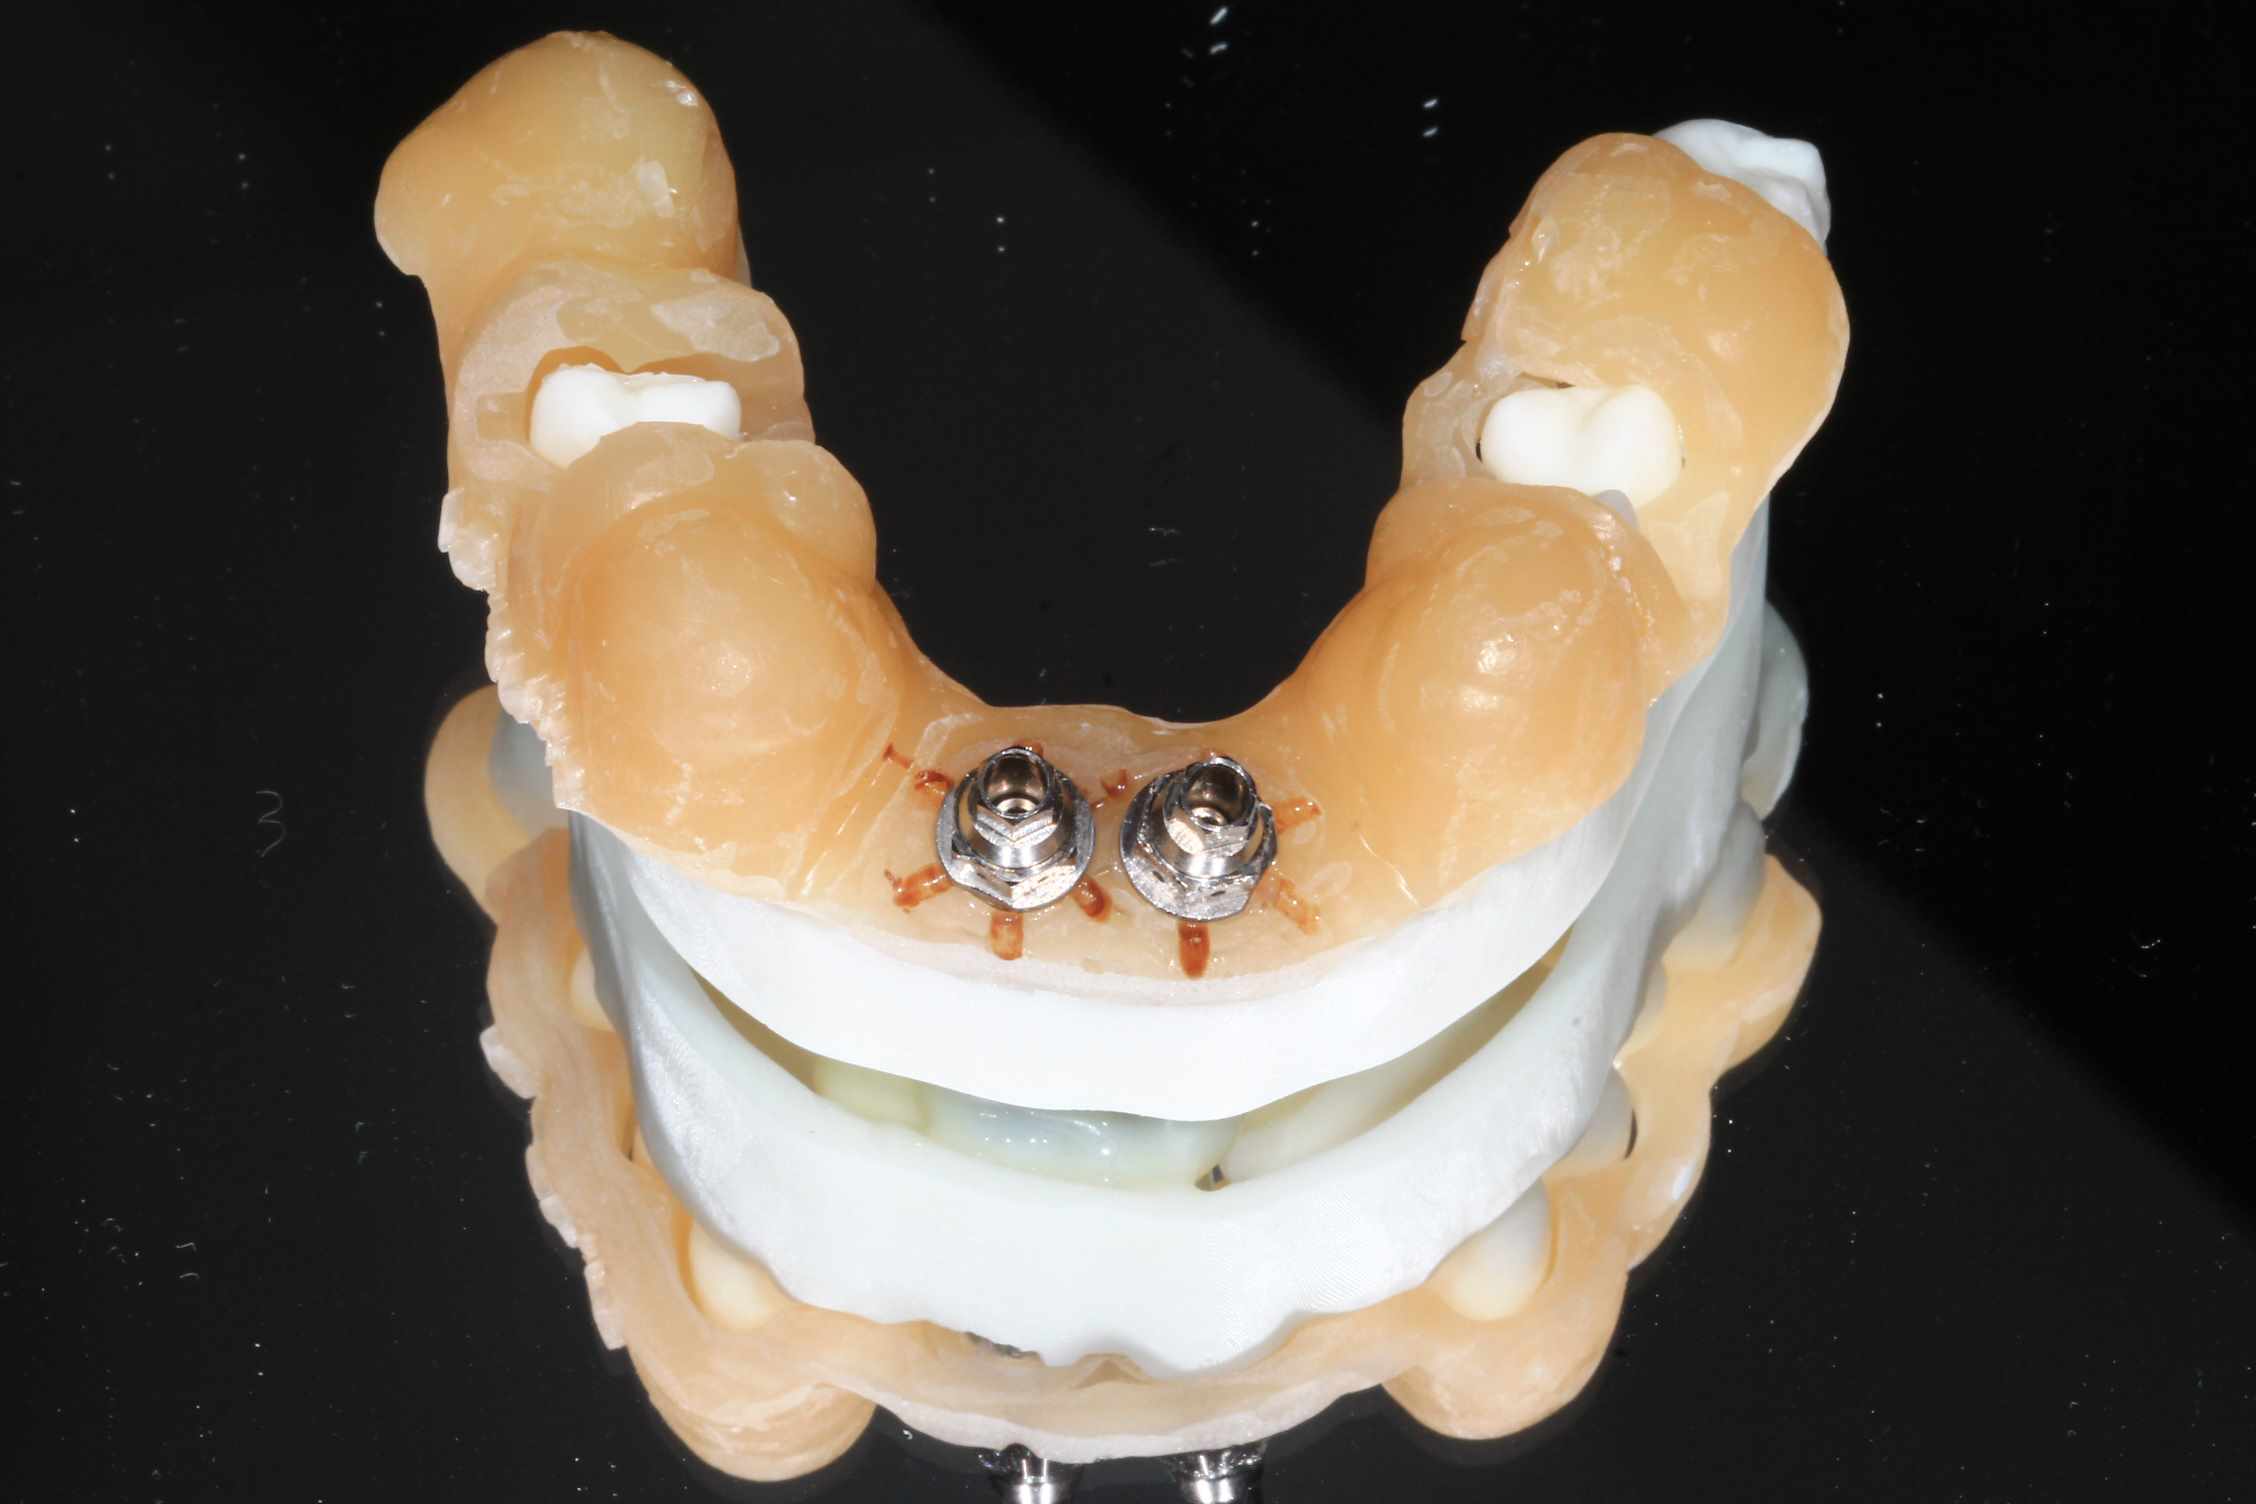

Mais celui la est tout chaud ( de vendredi dernier ) et j'ai regarder le temps que j'ai mis ( beaucoup plus complexe, donc plus long ). on va l'appeller Cas 2.

3 h de planif, modélisation du guide, puis 2 h environ pour la simulation de la chir , le modelisation et l'impression du bridge, qui tombe pile, zero retouche occlusale.

Avec un plan de traitement qui est suceptible de débat :)

K6kpgtkjnab9c7k5g9g0farlwmd6 - Eugenol

5t2rri9fzy9pxvmca7cis5gqte3m - Eugenol

4impvumlupunrh9dh8g6zpsz2sjx - Eugenol

Xvkhqtlsb1gx2pa0dwzncq4rtqsr - Eugenol

Xstwdtmbdmp87rg6dht5m703i0m9 - Eugenol

Ibyln43l47opnzvb28uh8b02v9kd - Eugenol